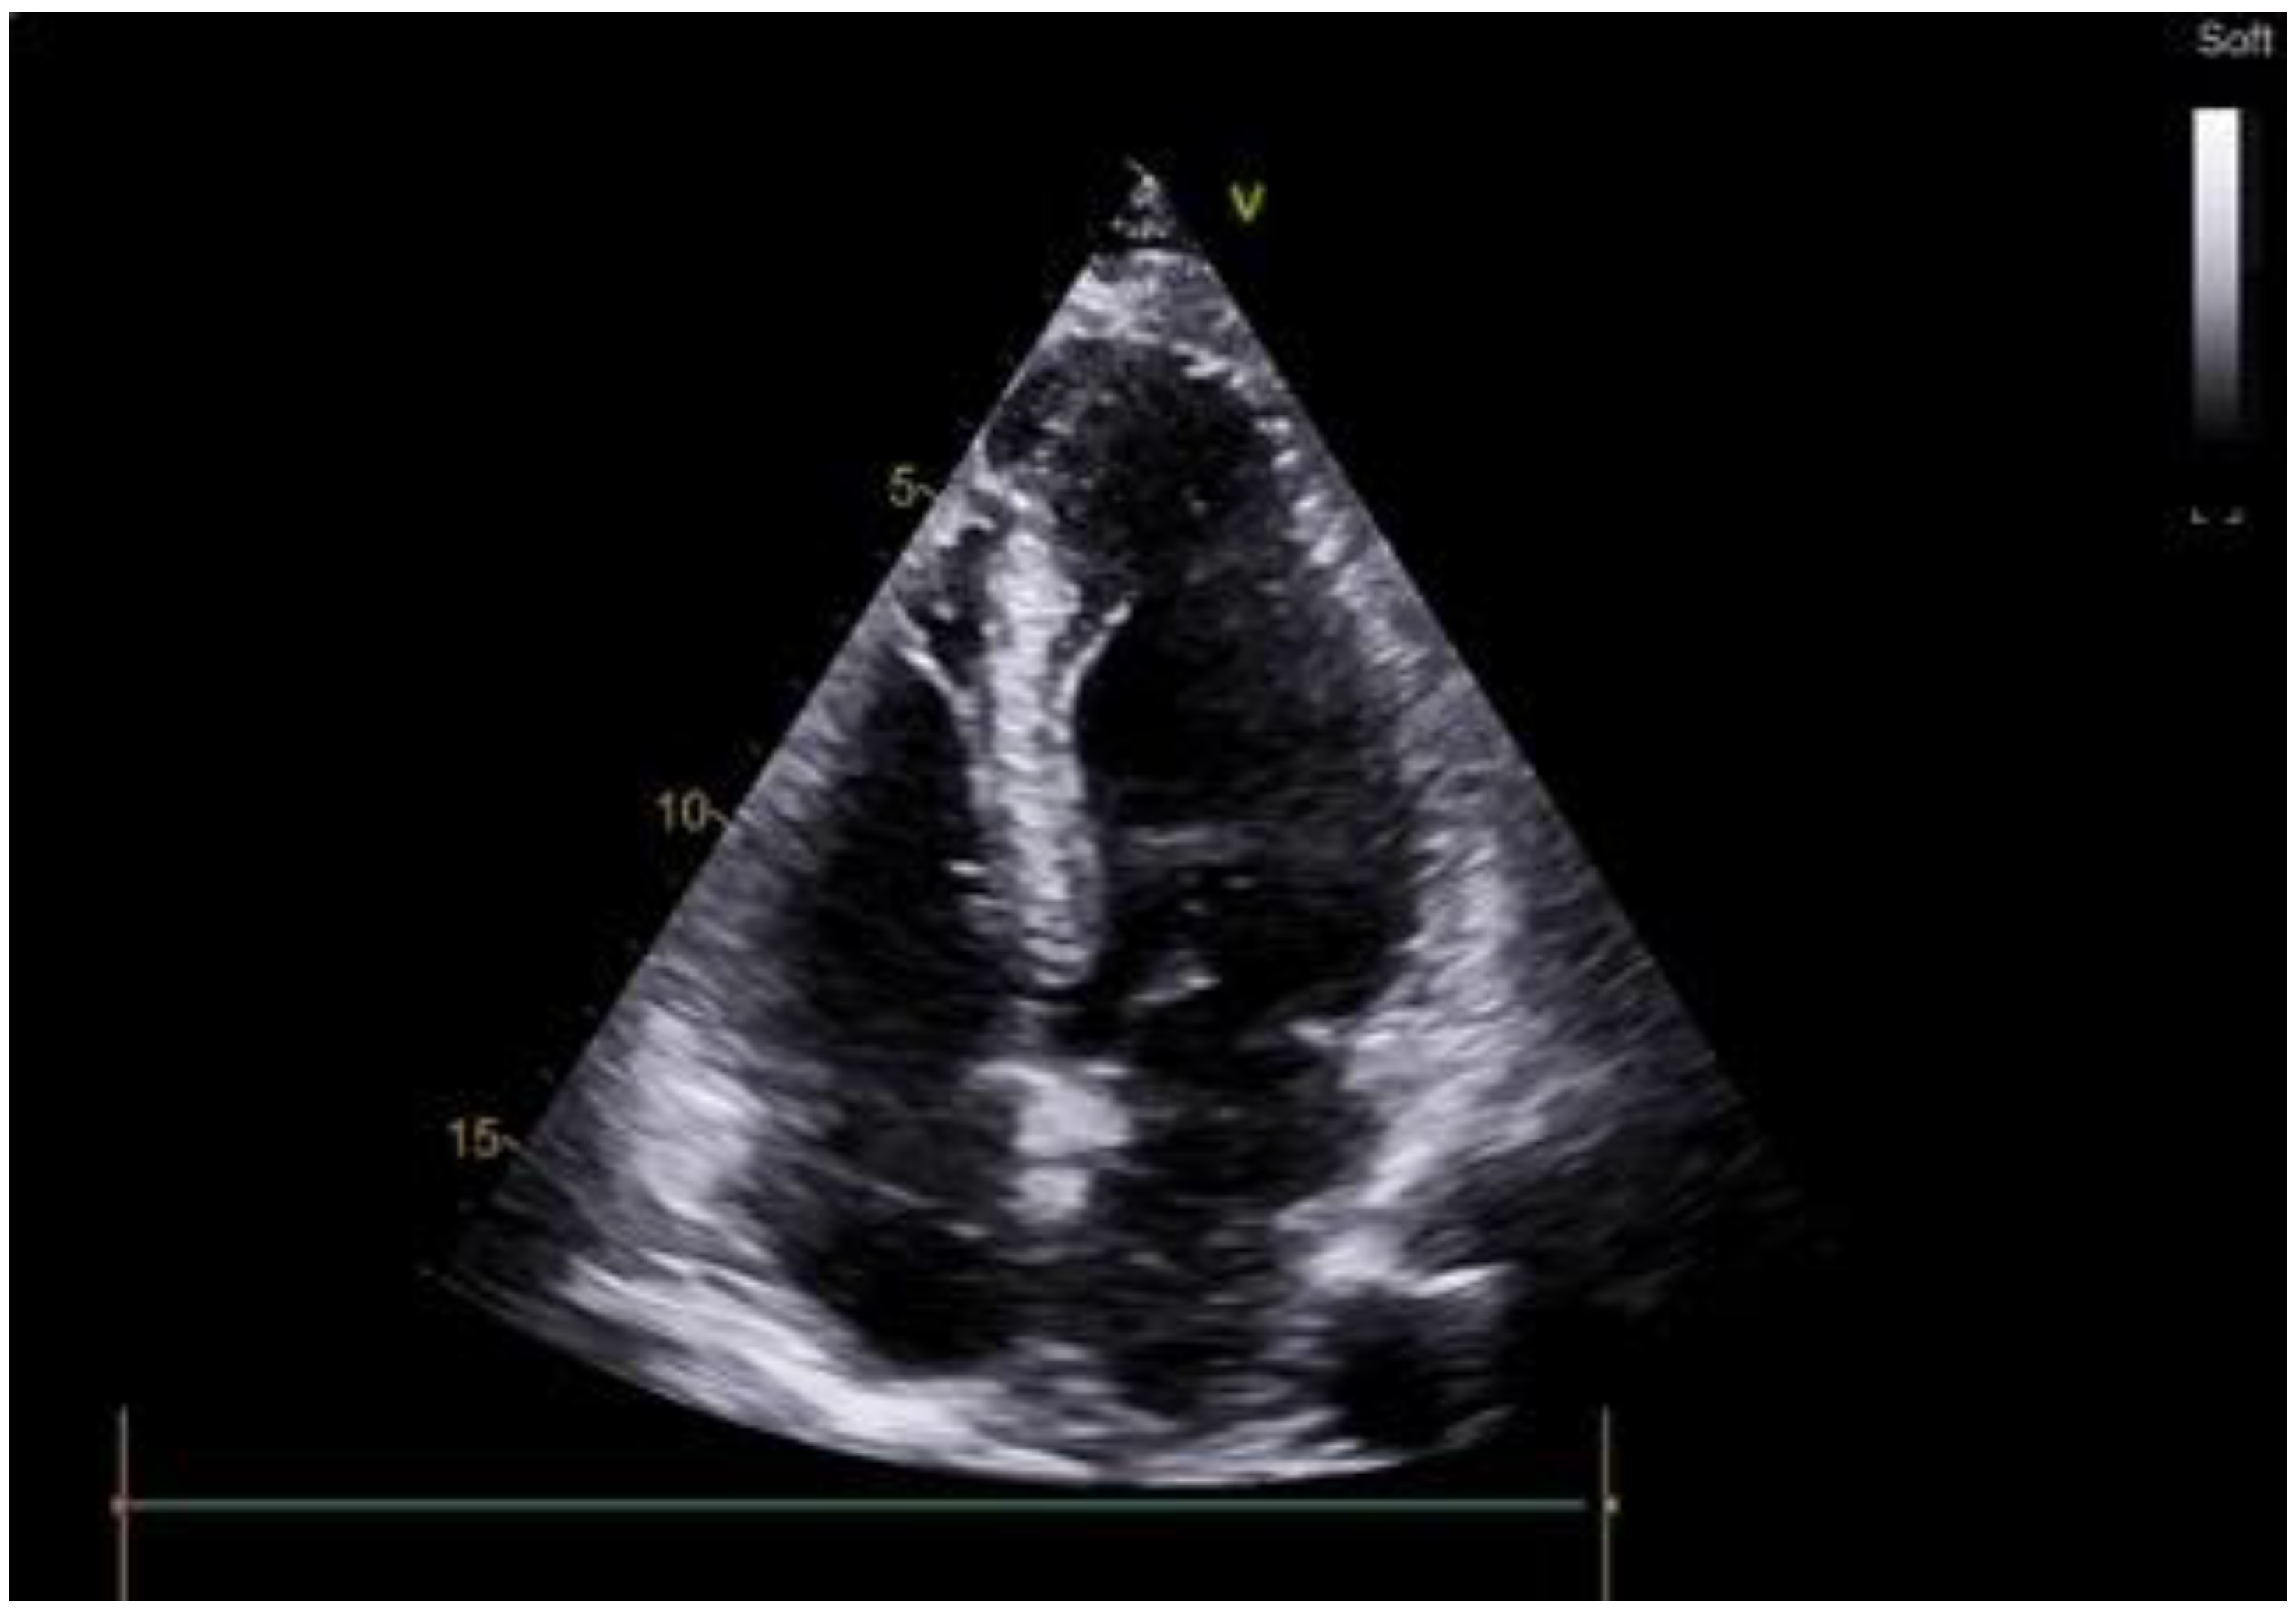

Figure 1.

Preoperative echocardiography of patient with apical hypertrophic cardiomyopathy.

A 63-year-old female with marked limitations in daily activities, fatigue, and shortness of breath while walking a short distance (approximately 50 m) was admitted to the hospital and diagnosed as New York Heart Association (NYHA) class III-IV. An electrocardiogram showed high QRS voltage and negative T waves in the precordial leads. Transthoracic echocardiography revealed an apical HCM variant with a left ventricular end-diastolic volume (LVEDV) of 59 mL, increased left atrial volume index of 44 mL/m2, average E/e’ > 14, LV ejection fraction (LVEF) of 69% without LVOTO (maximum exercise provokable LVOT gradient 15 mmHg), a reduced stroke volume (SV) index of 22 mL/m2, Grade 1 (mild) mitral regurgitation findings, and no systolic anterior motion syndrome. There was no evidence of subaortic obstruction. The maximum septal thicknesses in the basal, midventricular, and apical parts were 15, 15, and 19 mm, respectively (Figure 1, Supplementary Video S1). Coronary angiography revealed a right-dominant circulation without pathological outlines. A cardiac MRI confirmed apical HCM with maximum septal thicknesses in the basal, midventricular, and apical parts of 9, 14, and 20 mm, respectively; maximum LV lateral wall thicknesses of 6, 6, and 21 mm, respectively; maximum LV posterior wall thicknesses of 5, 6, and 18 mm, respectively; and maximum LV anterior wall thicknesses of 6, 6, and 18 mm, respectively (Figure 2, Supplementary Video S2).